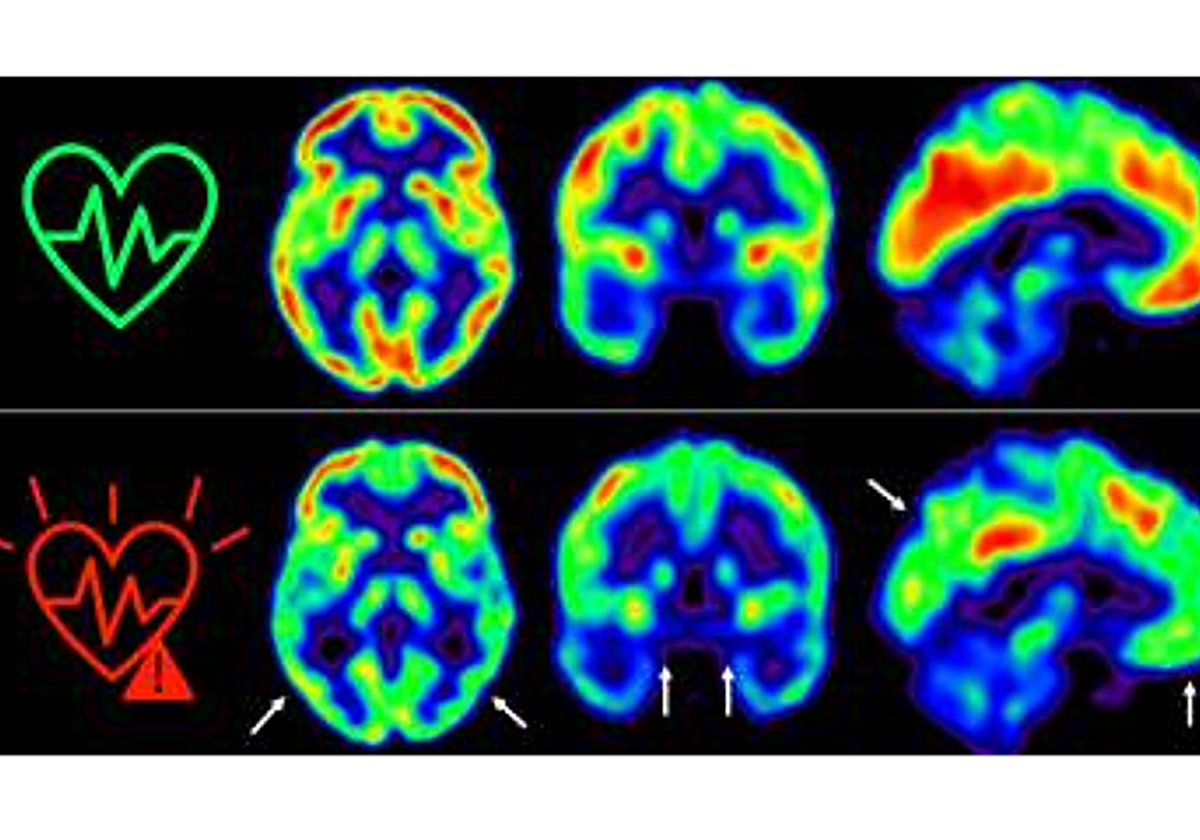

En 2021, los investigadores del CNIC descubrieron que la presencia de factores de riesgo cardiovascular y de aterosclerosis subclínica -antes de que aparezcan los síntomas- en las arterias carótidas, que son las que suministran sangre al cerebro, en individuos de 50 años aparentemente sanos que participan en el estudio PESA-CNIC-Santander, estaba asociada a un menor metabolismo de glucosa cerebral. El metabolismo de la glucosa cerebral está considerado un indicador de salud cerebral.

El PESA-CNIC-Santander ha seguido a estos individuos a lo largo de 5 años y ha encontrado que aquellos que mantienen un riesgo cardiovascular elevado durante todo este tiempo sufren una disminución aún mayor del metabolismo cerebral medido a través de técnicas de imagen como tomografía por emisión de positrones (PET).

«Hemos detectado un declive metabólico cerebral tres veces mayor que el de personas que se mantienen en bajo riesgo cardiovascular», señala Catarina Tristão-Pereira, primera firmante del artículo.

Además, el equipo descubrió que la progresión de la aterosclerosis subclínica en las carótidas durante estos 5 años se relacionaba con una disminución del metabolismo en regiones cerebrales vulnerables a la enfermedad de Alzheimer, de manera aditiva al efecto de los propios factores de riesgo cardiovascular. «Estos resultados corroboran que la detección por imagen de la aterosclerosis subclínica aporta información muy relevante», añade Fuster.